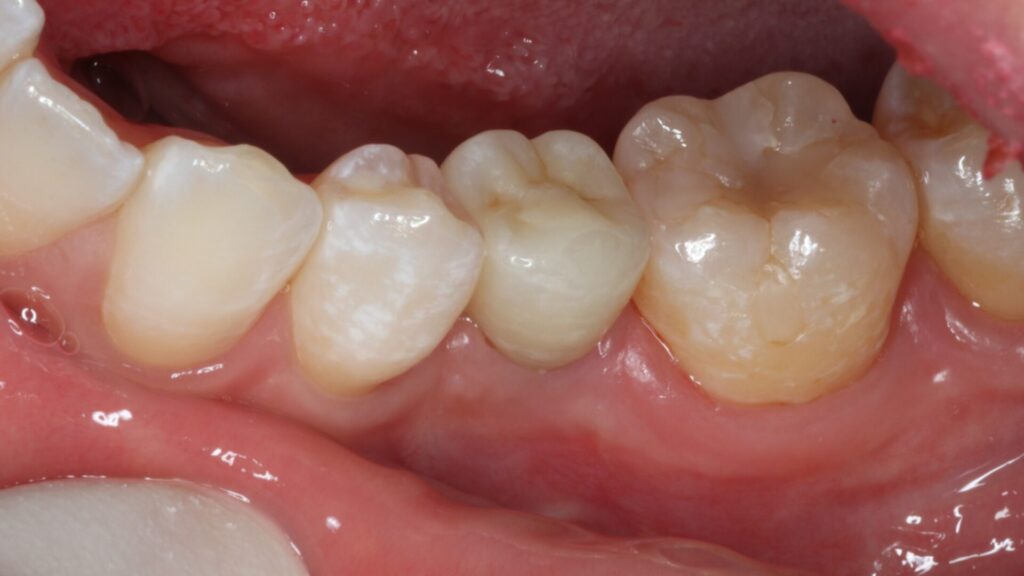

治療後

術後4ヵ月で最終的なセラミック冠を装着しています。

機能的にも見た目も満足いただける仕上がりになりました。